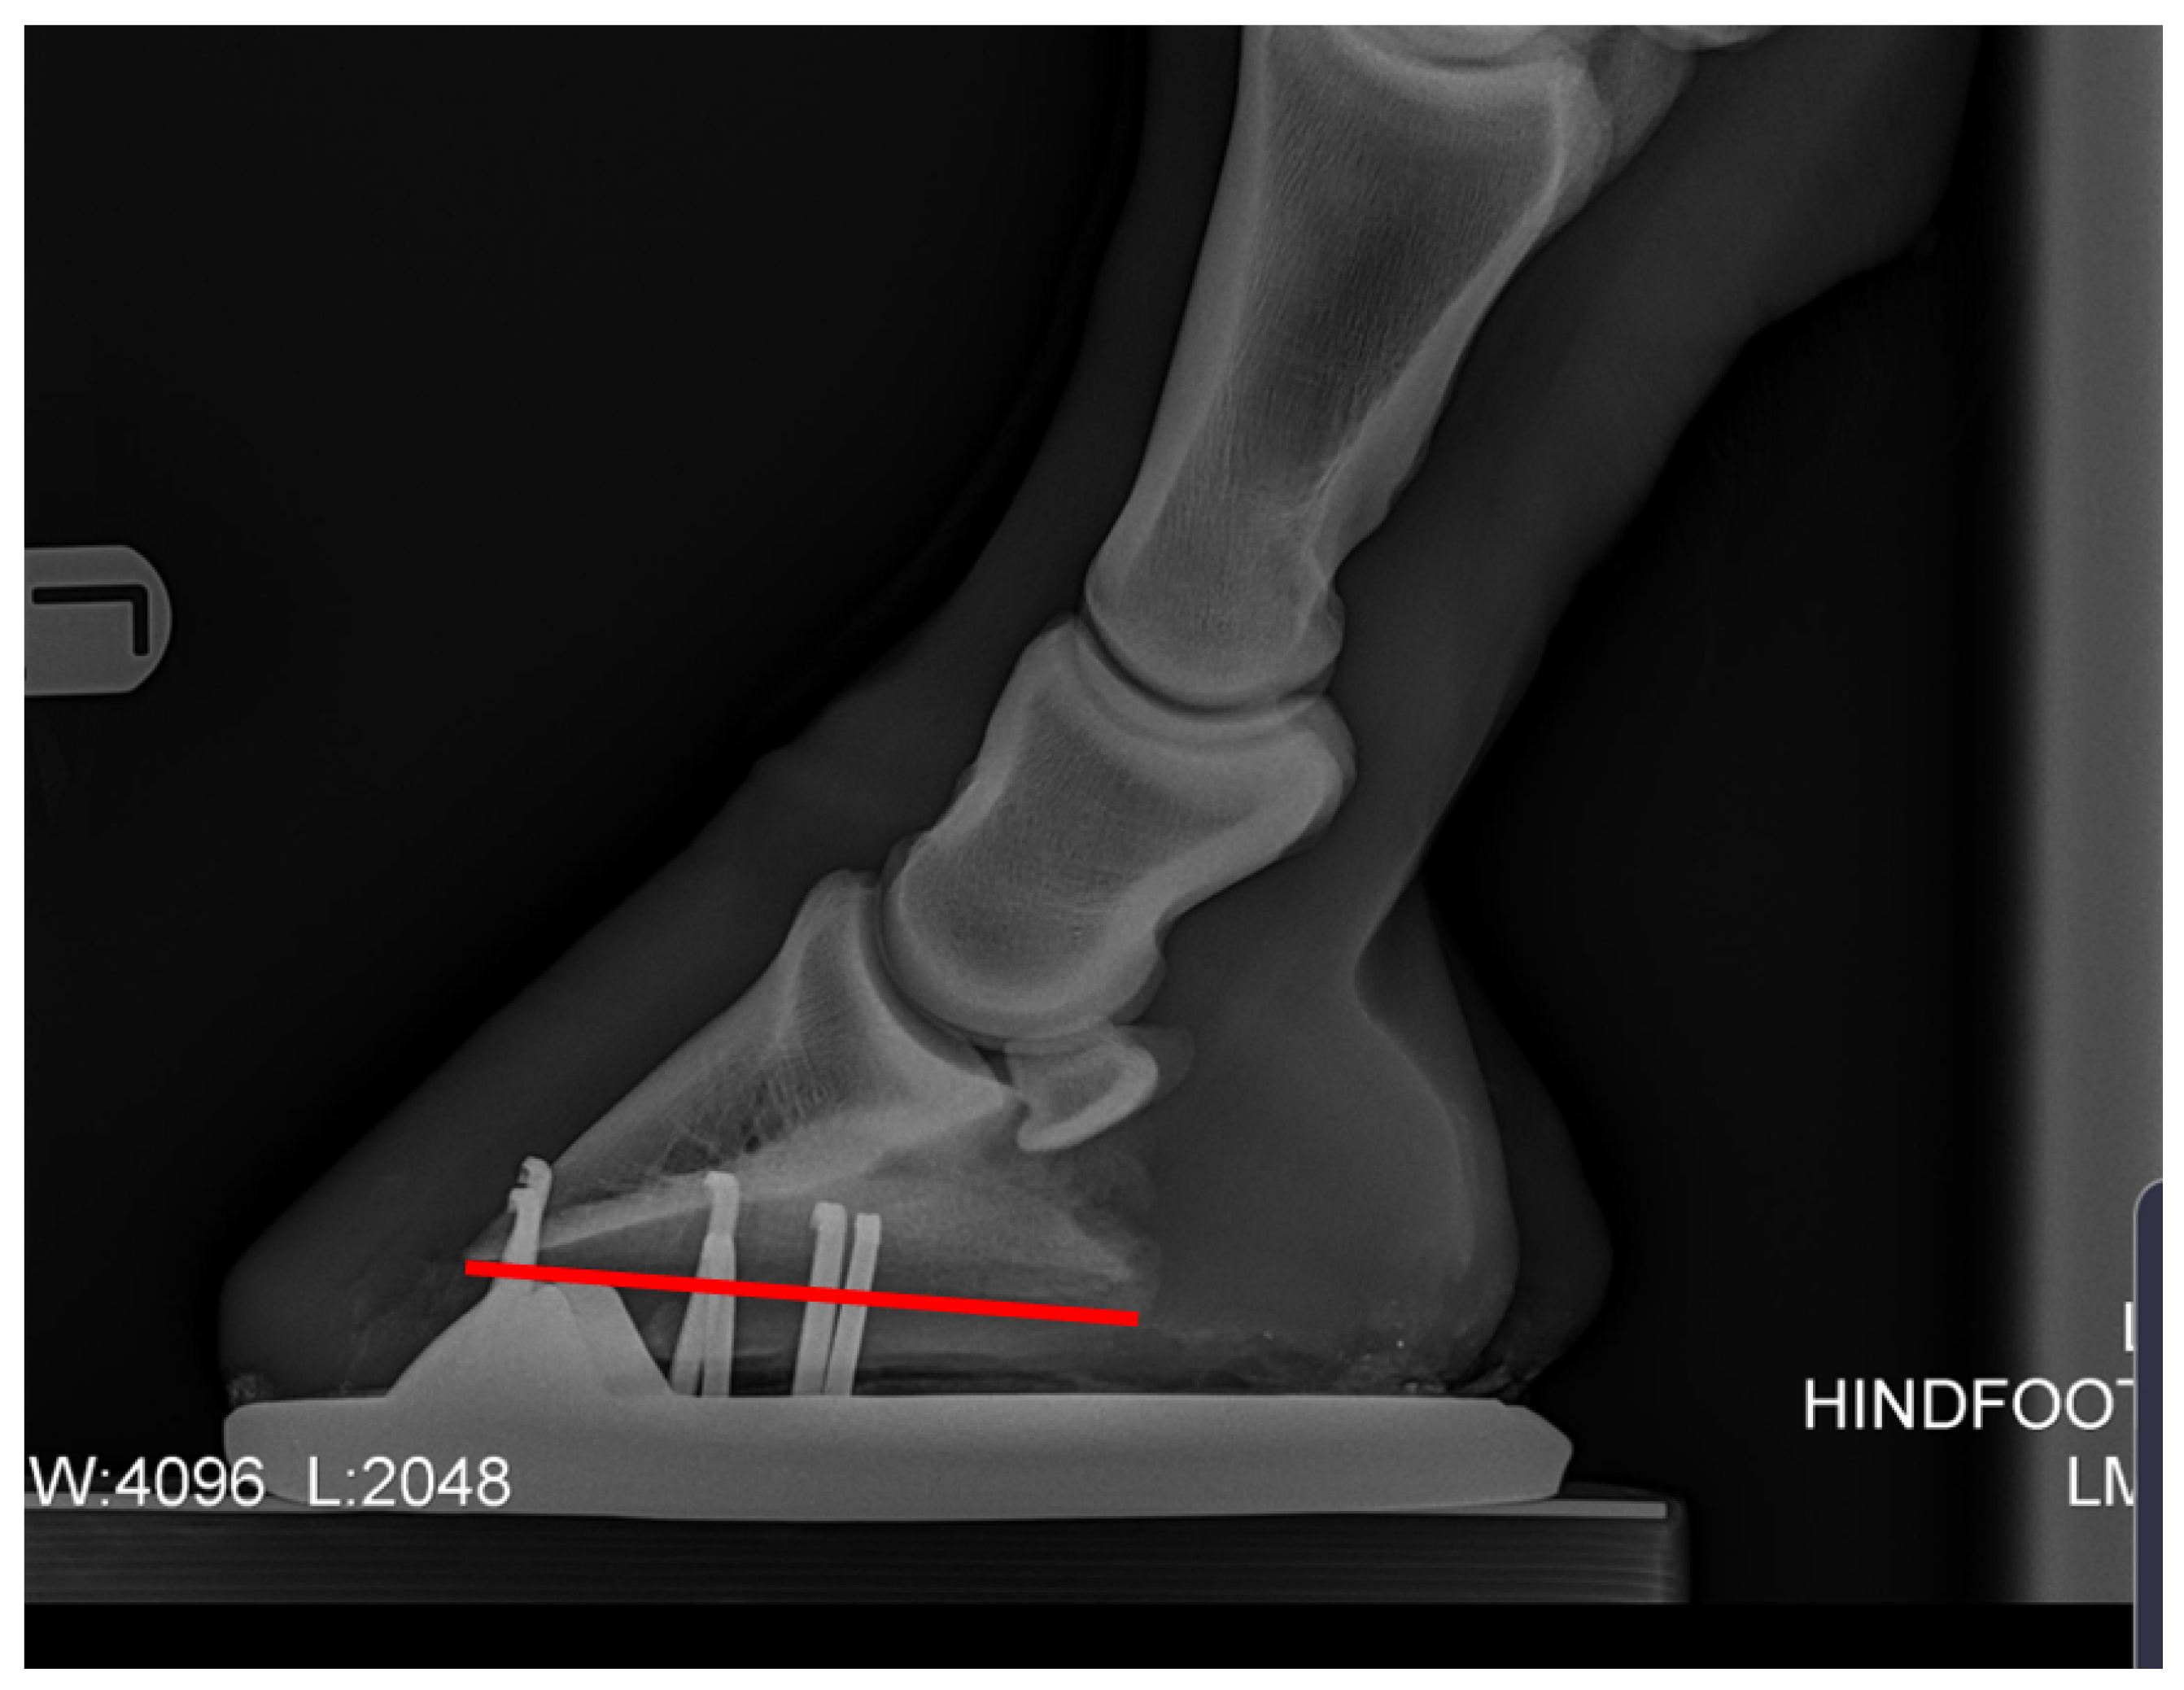

Recent studies indicating that change in posture is associated with poor hind hoof balance have focused on negative plantar angles [2,5] and their link to pathologies in the hind limb. Negative plantar angle (NPLA) is defined as a negative angle to the distal phalanx (Figure 2).

Figure 2. Negative plantar angle takes its name from a principal radiographic feature—the solar or plantar margin of the third phalanx (P3) has a negative angle in relation to the ground surface, and sole depth under the dorsal-distal margin (tip) of P3 is greater than that under the palmar processes (wings) when viewed on a lateral radiograph [23].

Animals 12 03275 g002